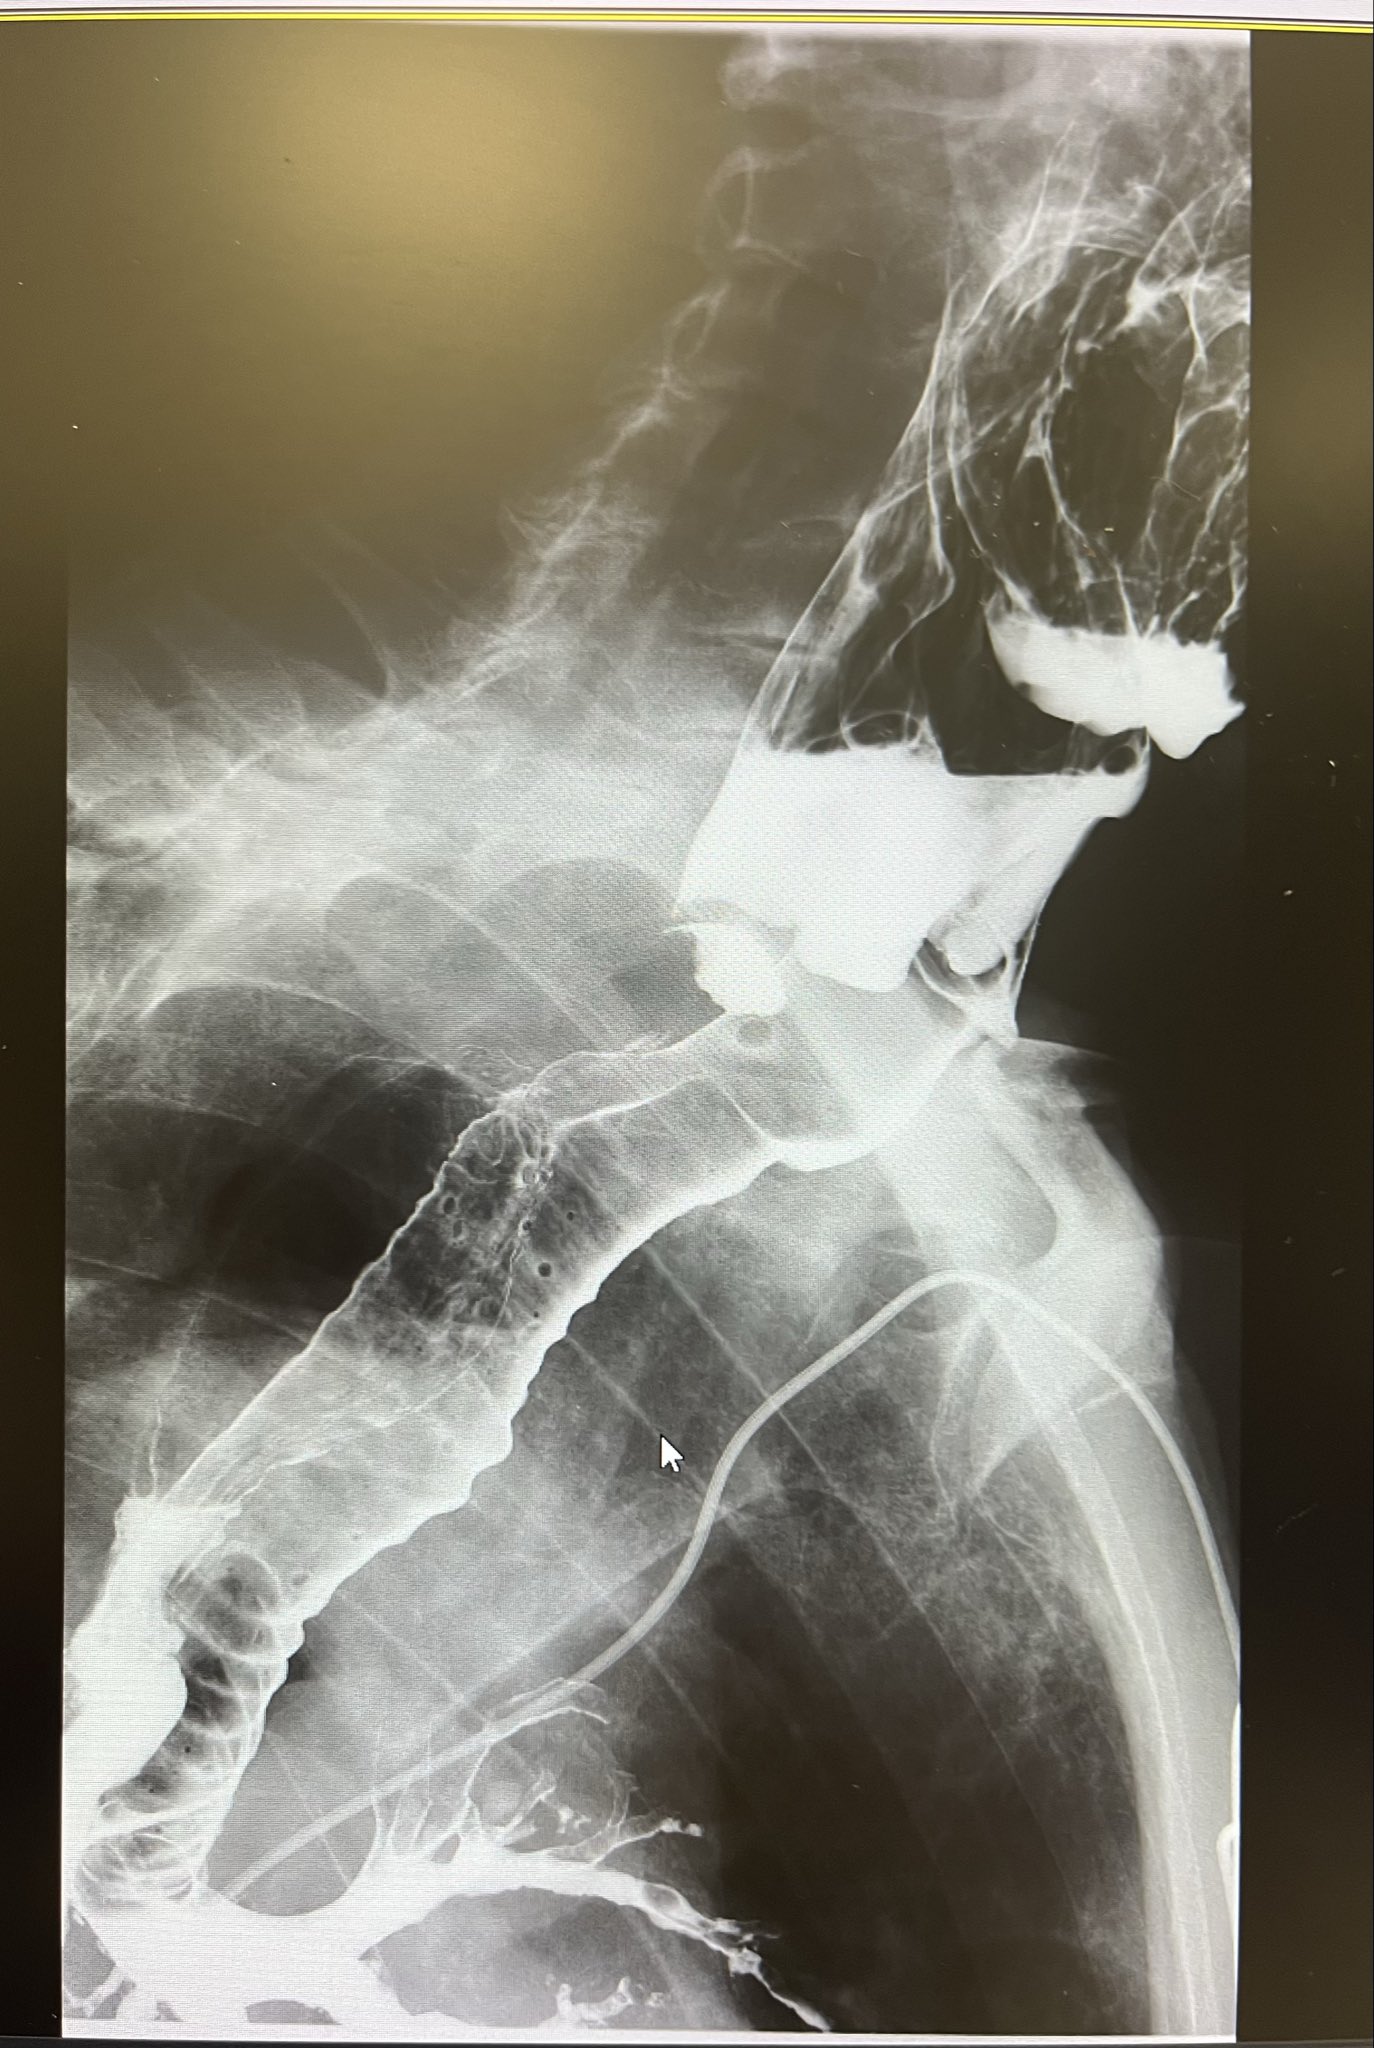

Hepatic vein thrombosis in a young or otherwise unexplained case should prompt a hypercoagulability workup.